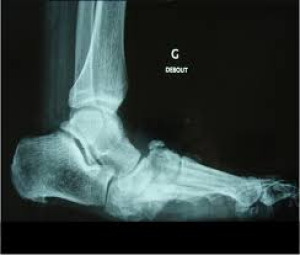

Complément : Cas particulier : le Pied de Charcot

Cette complication du diabète correspond à une atteinte ostéo-articulaire évolutive et destructrice du pied dont l'origine est neuropathique et inflammatoire.

La maladie comprend deux phases :

une première phase aiguë : le patient présente un pied douloureux , chaud avec un œdème, sans plaie.

une deuxième phase chronique : une reconstruction anarchique ostéo-articulaire se produit aboutissant à une déformation souvent sévère du pied.

Le traitement de la phase aigue est une mise en décharge immédiate et complète du pied à l'aide d'un plâtre de décharge ou une botte de décharge jusqu'à régression complète des symptômes (plusieurs semaines voire plusieurs mois).

Tout pied ou cheville œdématié et sans plaie chez un patient diabétique doit faire évoquer un « pied de Charcot » en phase aigue jusqu'à preuve du contraire.